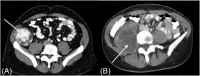

Patients with retroperitoneal sarcoma can present to a variety of clinicians with non-specific symptoms and retroperitoneal sarcomas can be incidental findings. Failure to recognize retroperitoneal sarcomas on imaging can lead to inappropriate management in non-specialist centers. Therefore it is critical that the possibility of retroperitoneal sarcoma should be considered with prompt referral to a soft tissue sarcoma unit. This review guides clinicians through a diagnostic pathway, introduces concepts in response assessment and new imaging developments.